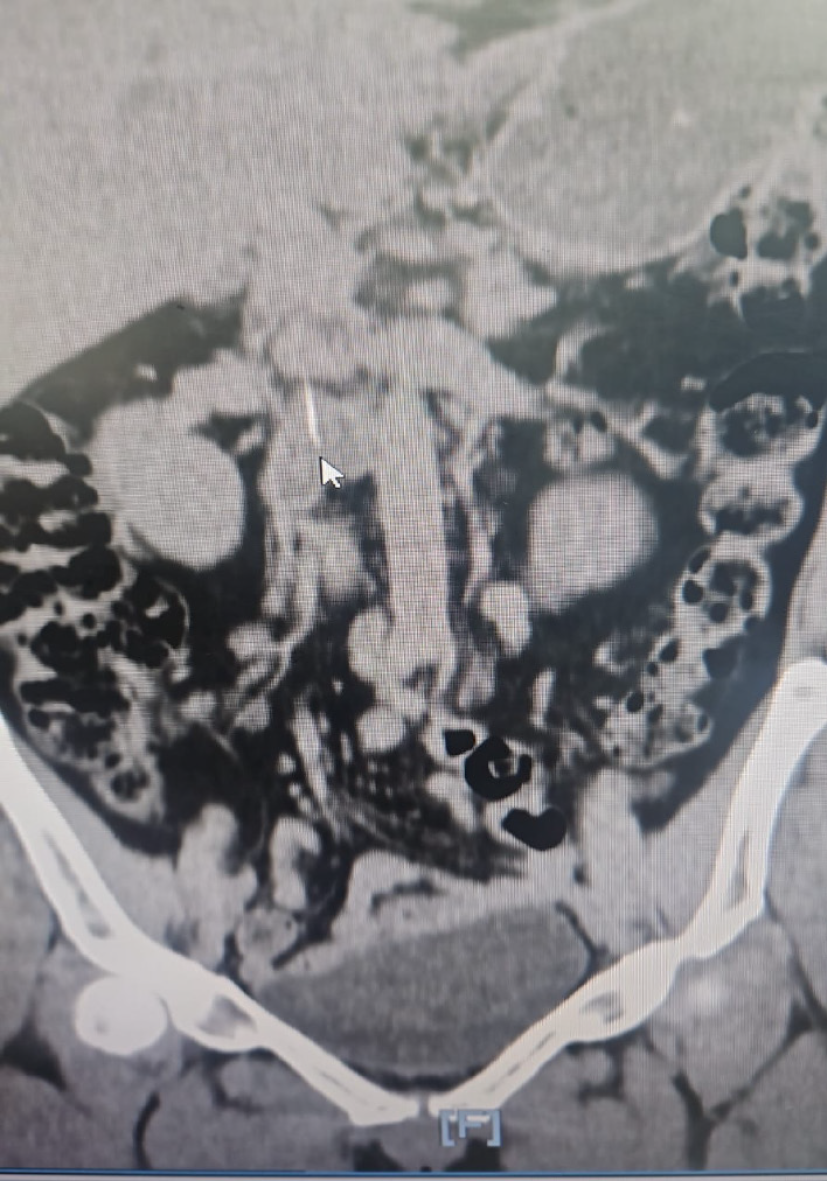

Magnetic resonance cholangiopancreatography (MRCP) showed no hepatico-jejunostomy stricture or biliary dilatation but revealed a 37-mm linear filling defect in the right intrahepatic duct, initially suspected as intrahepatic lithiasis. Percutaneous transhepatic cholangiography was planned but abandoned after ultrasound revealed no ductal dilation. An incidental right hydronephrosis prompted CT kidneys, ureters, and bladder (KUB), which, upon careful second review, demonstrated a subtle, linear hyperdense structure traversing the efferent jejunal limb toward the right renal vein, consistent with a fish bone (Figure 1). This clarified the previously ambiguous intrahepatic filling defect, which likely represented inflammatory changes secondary to jejunal perforation. Deep push enteroscopy using an Olympus PCFPH190 L pediatric colonoscope revealed a fish bone deeply embedded in the jejunal wall of the efferent limb (Figure 2A). The specimen was meticulously extracted intact using biopsy forceps (Figure 2B and C) (Video).